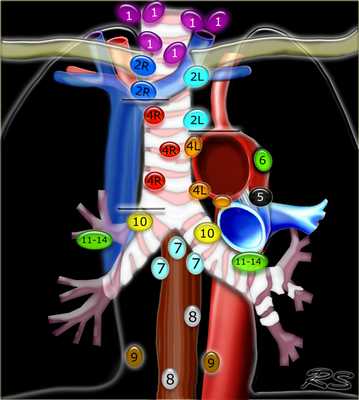

На рисунке шеи (вид сбоку под углом) показано положение важных групп лимфоузлов шеи. Лимфоузлы во внутренней яремной цепочке делятся на верхние, средние и нижние плоскостью подъязычной кости и перстневидного хряща. Лимфоузлы добавочной спинальной цепочки плоскостью перстневидного хряща аналогично делятся на нижние и верхние. На рисунке (вид сбоку) изображены лимфоузлы лица и околоушной железы. Эти лимфоузлы не нумеруются по уровням, а описываются согласно расположению. На рисунке (вид сбоку под углом) шеи показан аксиальный срез в надподъязычной области. Учитывайте, что заглоточные лимфоузлы позади глотки часто являются клинически «немыми». Выделены плоскости подъязычной кости (синяя дуга) и перстневидного хряща (оранжевый круг), разделяющие внутреннюю яремную и добавочную спинальную группы лимфатических узлов.

На первой из трех аксиальных КТ с КУ надподъязычной области шеи, представленных сверху вниз, визуализируются внутренняя яремная (уровень II) и добавочная спинальная (уровень V) цепочки лимфоузлов. Яремно-двубрюшный («сторожевой») лимфоузел-самый высокий во внутренней яремной (глубокой шейной) цепочке. Визуализируются внутренние яремные и добавочные спинальные лимфоузлы наряду с поднижнечелюстными лимфоузлами (уровень IA) спереди и снаружи от поднижнечелюстной железы в заднем шейном пространстве с обеих сторон. Сразу же над подъязычной костью между передним брюшком правой и левой двубрюшной мышцы визуализируется подбородочный лимфоузел (уровень IA). Обратите также внимание на поднижнечелюстные (уровень IB), верхние внутренние яремные (уровни IIА, IIВ), добавочные спинальные (уровень VA) лимфоузлы. На аксиальной Т1 МРТ на уровне нижней части ротоглотки визуализируются лимфоузлы с характерным Т1 сигналом низкой интенсивности. Слева хорошо заметен поднижнечелюстной лимфоузел с жировыми воротами. С обеих сторон видны внутренние яремные лимфоузлы уровня IIA. На аксиальной Т2 МРТ на уровне нижней части ротоглотки с обеих сторон визуализируются верхние внутренние яремные лимфоузлы с промежуточной интенсивностью сигнала. На аксиальной Т2 МРТ с жироподавлением лимфоузлы становятся более заметными. STIR также позволяет добиться улучшения визуализации лимфоузлов. На Т2 с жироподавлением отчетливее выделяется ткань язычной миндалины.

Шея, латеральный косой вид. Аксиальный срез через надподъязычную область шеи. Обратите внимание, что в латеральной части шеи основные цепи лимфатических узлов формируют треугольник (цепь внутренней яремной вены, цепь добавочного нерва, поперечной шейной артерии). Плоскости подъязычной кости (синяя дуга) и перстневидного хряща (оранжевая дуга) подразделяют внутреннюю яремную и добавочную цепи на хирургические уровни. Шея, латеральный вид, хирургические уровни лимфатических узлов. Цепи и группы лимфоузлов подразделены не по их анатомическому расположению, как на предыдущем рисунке, а по хирургическим ориентирам. Подъязычная кость отделяет уровень Iа от уровня VI и уровень II от уровня III. По нижнему краю перстневидного хряща проходит граница уровней III и IV, а также Va и Vb. Задний край грудино-ключично-сосцевидной мышцы отделяет уровни II, III и IV от уровня V. Сонная артерия отделяет уровень VI от уровней III и IV. Нижний край нижней челюсти отделяет уровень lb от лицевых лимфоузлов.

С хирургической точки зрения лимфатические узлы шеи подразделяются на шесть уровней (или зон). Границами для уровней выступают хирургические ориентиры. Для того, чтобы определить уровни лимфоузлов на изображениях, используются радиологические ориентиры, которые приблизительно соответствуют хирургическим.

• Уровень I: подподбородочные (уровень Iа) и поднижнечелюстные (уровень lb), расположенные книзу от нижней челюсти; получают лимфу от губ, дна полости рта, ротовой части языка; лимфа опекает в лимфоузлы уровня II.

• Уровень II: верхние лимфоузлы внутренней яремной цепи (уровень IIа) и добавочного нерва (уровень IIb); кпереди или глубже грудино-ключично-сосцевидной мышцы, кверху от подъязычной кости; получают лимфу от всех вышележащих узлов и от глотки; опок в лимфоузлы уровня III.

• Уровень III: средняя треть узлов внутренней яремной цепи; кпереди или глубже грудино-ключично-сосцевидной мышцы; ниже подъязычной мышцы, но выше нижнего края перстневидного хряща; получают лимфу от гортани и узлов уровня II; отток в лимфоузлы уровня IV.

• Уровень IV: нижняя треть узлов внутренней яремной цепи и медиальной части цепи поперечной артерии шеи; кпереди или глубже грудино-ключично-сосцевидной мышцы, книзу от перстневидного хряща; получают лимфу от узлов уровня III, грудной клетки и брюшной полости.

• Уровень V: нижняя часть узлов добавочного нерва (уровень Va) и задней части узлов поперечной артерии шеи (уровень Vb); расположены в заднем шейном пространстве, четко сзади от заднего края грудино-ключично-сосцевидной мышцы; получают лимфу от затылочных, заглоточных, околоушных и парааурикулярных лимфоузлов; опок в узлы уровня IV и средостения.

• Уровень VI: паратрахеальная цепь; кнаружи от мышцы, крепящихся к подъязычной кости, между сонными артериями, латеральнее трахеи в трахеопищеводной борозде; получают лимфу от висцерального пространства (особенно от щитовидной железы), опок в лимфоузлы уровня IV и средостения.

• В лучевой онкологии «надключичные лимфоузлы» трактуются как самостоятельная группа лимфоузлов, но в лучевой диагностике их относят к уровням IV и V.